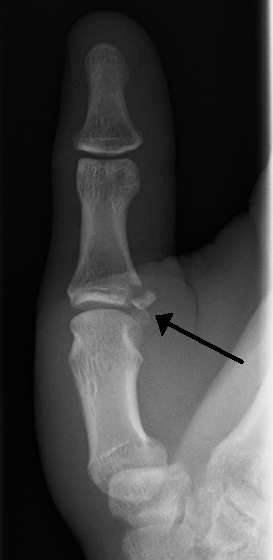

| Avulsion fractures of the ulnar base of the proximal phalanx of the thumb ( Gamekeeper's fracture ) | |

When approaching this type of injury, the physician must first determine whether there is an incomplete rupture (or sprain) of the UCL, or a complete rupture. If the UCL is completely disrupted, the physician must then determine whether there is interposition of the adductor aponeurosis (Stener lesion), or simply a complete rupture of the UCL with anatomic or near-anatomic position. Radiographs are helpful in determining the possible presence of an avulsion fracture of the proximal phalanx insertion site of the ulnar collateral ligament. Stress examination, or one done under fluoroscopic guidance, can help determine the integrity of the ligament.